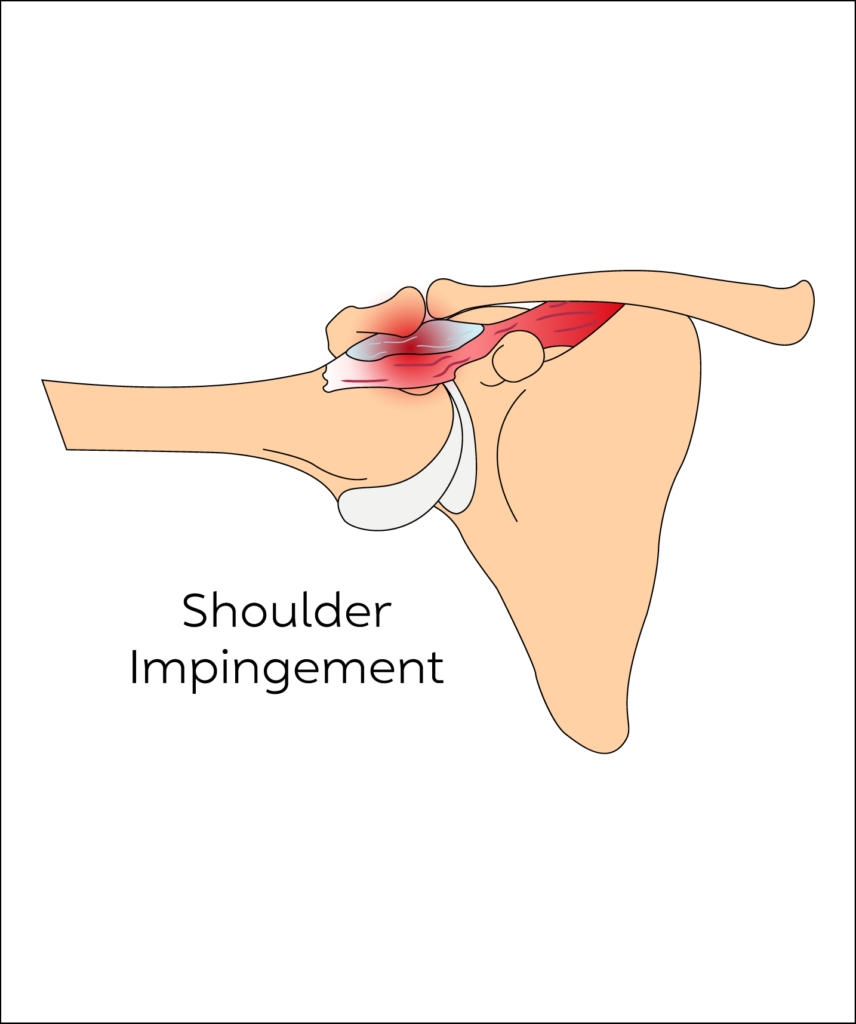

Shoulder Impingement & Bursitis

It includes a wide range of conditions that results in shoulder pain and restricted movements. These include rotator cuff tears (tendon tears), inflamed bursae secondary to tendonitis such as calcific tendonitis or tendonitis due to overuse as in the case of the supraspinatus tendon otherwise known as supraspinatus tendinitis (‘Painful Arc Syndrome’).

It can affect people of all ages

People will usually experience a dull aching pain when moving the shoulder, alongside some mild swelling. In more severe cases there is significant restriction of movement.

- If symptoms remain persistent for 3 months despite medication and physiotherapy, corticosteroid injections targeted using an ultrasound are a very effective form of treatment. They can help to significantly reduce inflammation and subsequently pain.